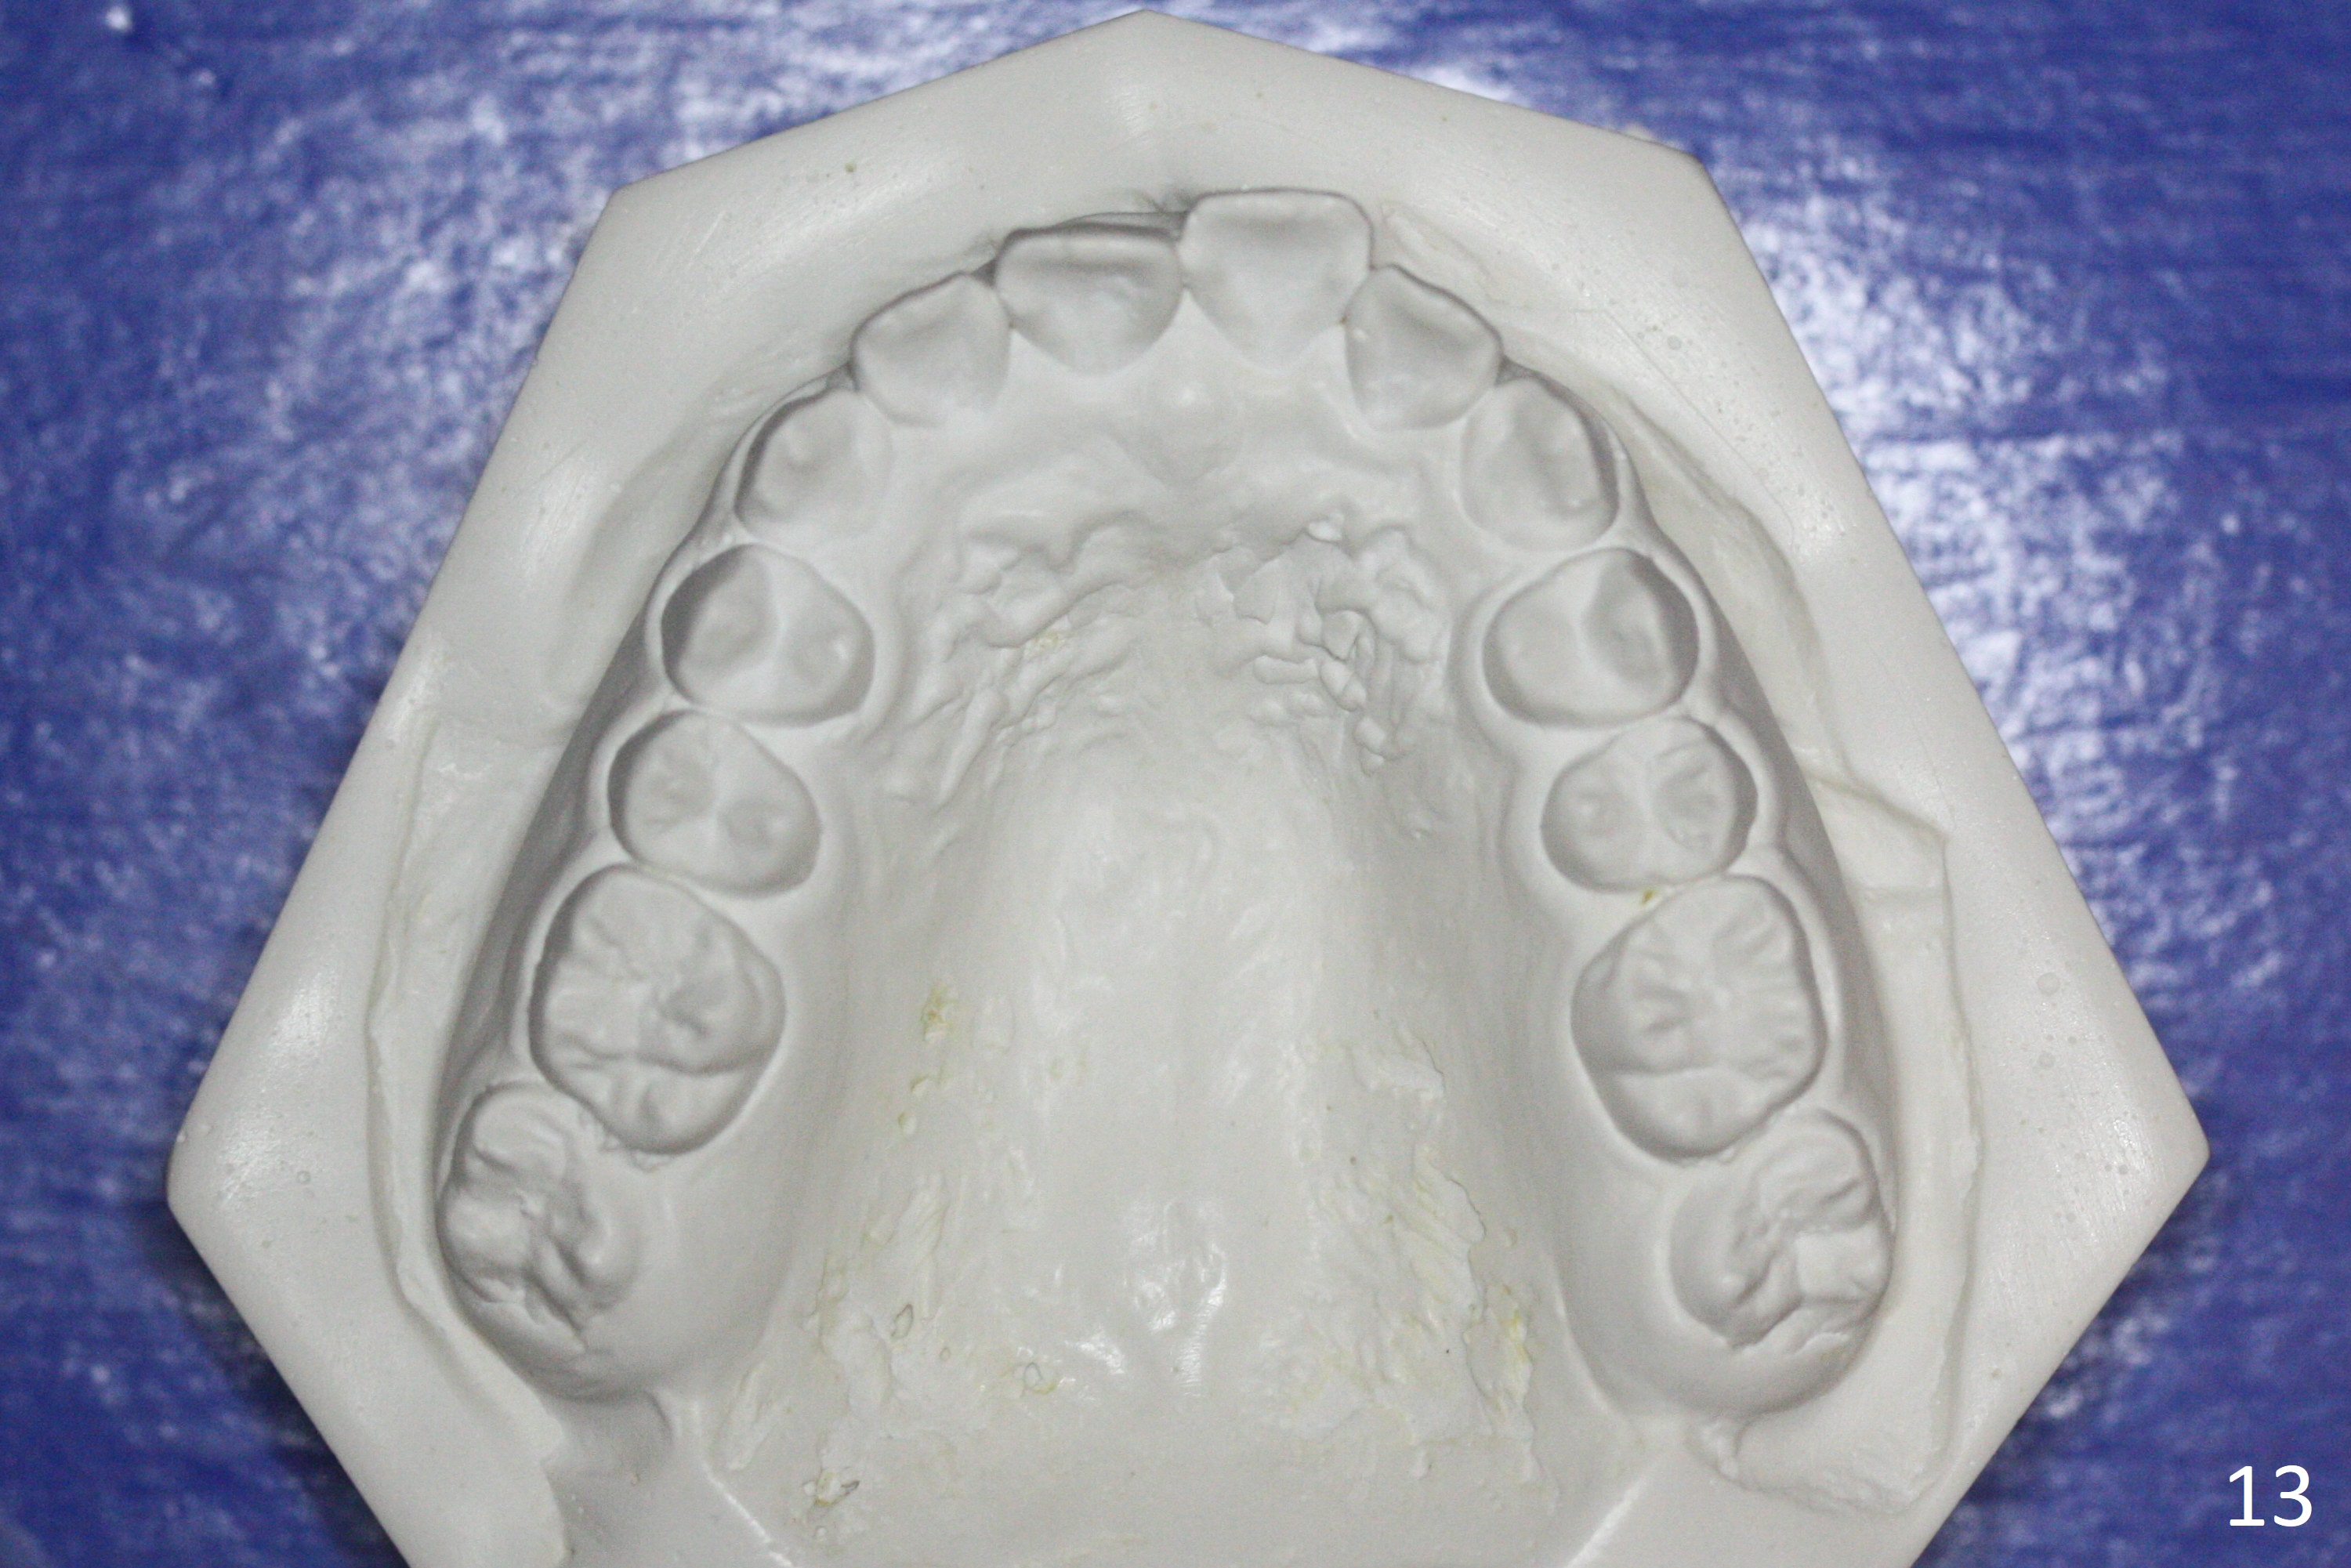

A 12-year-old woman has normal facial profile (Fig.1-6,12) and crowded dentition (7-11). Because of erupting 2nd molars (Fig.10,15), it is difficult to place rubber separators between U6/7. Copper ones are used instead (Fig.15 ^). Crowding and narrow arches (Fig.13,14) may be associated with the enlarged right Inferior Nasal Concha (Fig.15 *).